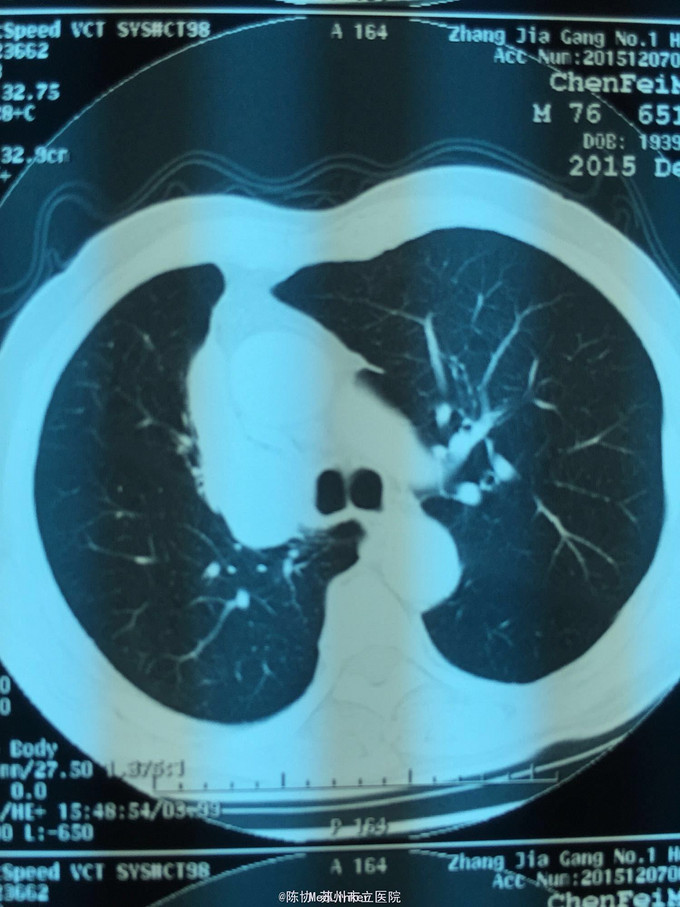

主诉:体检发现右上肺不张半月 77岁男,半月前体检发现右上肺不张,无不适。无消瘦,无咳血,无干咳。去年4月右上肺炎,抗生素治愈,当时CT未见肺肿块。入院支气管镜发现右上支气管开口组织增厚闭塞,开口近侧有隆起约3x3平方毫米,取活检5块病理示中度非典型增生。CT提示在右侧主支气管外侧有30x30平方毫米块影,压迫右上支气管开口处。三大常规和生化检查正常,肿瘤指标正常,TAP正常。

右侧中央型肺癌 重做支气管镜,精于定位找到病症组织,获得病理诊断来指导治疗。 胸外科医生不建议手术,理由是肿瘤位置靠近主支气管和气管,袖状切除不一定看干净。 请问正确的诊断,和比较合理的治疗方法是什么?求助大家思考评论